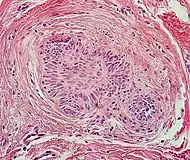

| Squamous-cell carcinoma of the skin | Squamous-cell carcinoma of the skin is generally distinguishable by for example relatively more cytoplasm, horn cyst formation and absence of palisading and cleft formations. Yet, a high prevalence means a relatively high incidence of borderline cases, such as basal-cell carcinoma with squamous cell metaplasia (H&E stain at left in image). BerEP4 staining helps in such cases, staining only basal-cell carcinoma cells (right in image). |  |